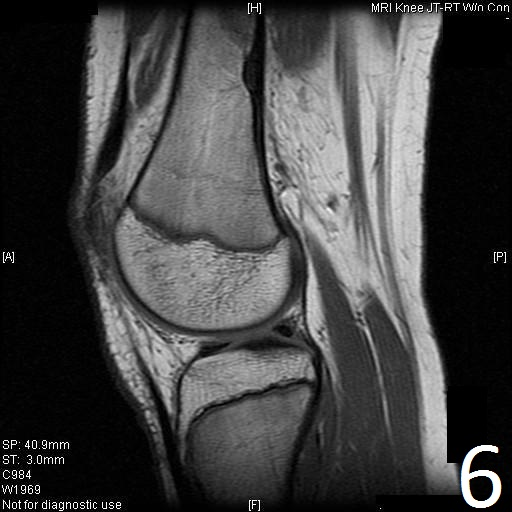

MRI

• Low- signal on T1 (Fig. 8)

• Variable heterogeneneous signal on T2 (Fig. 9).

• Possible extensive hypercellular fibrous tissue and hemosiderin seen on T2

• Can be useful for demonstrating an aneurysmal bone cyst component

Fig. 6-9: Sagittal T1 (Fig. 6) and T2 (Fig. 7) MRI of the knee demonstrates a fibrous cortical defect. Axial T1W (Fig. 8) and T2W (Fig. 9) show a heterogeneous lesion on distal femur, compatible with nonossifying fibroma.